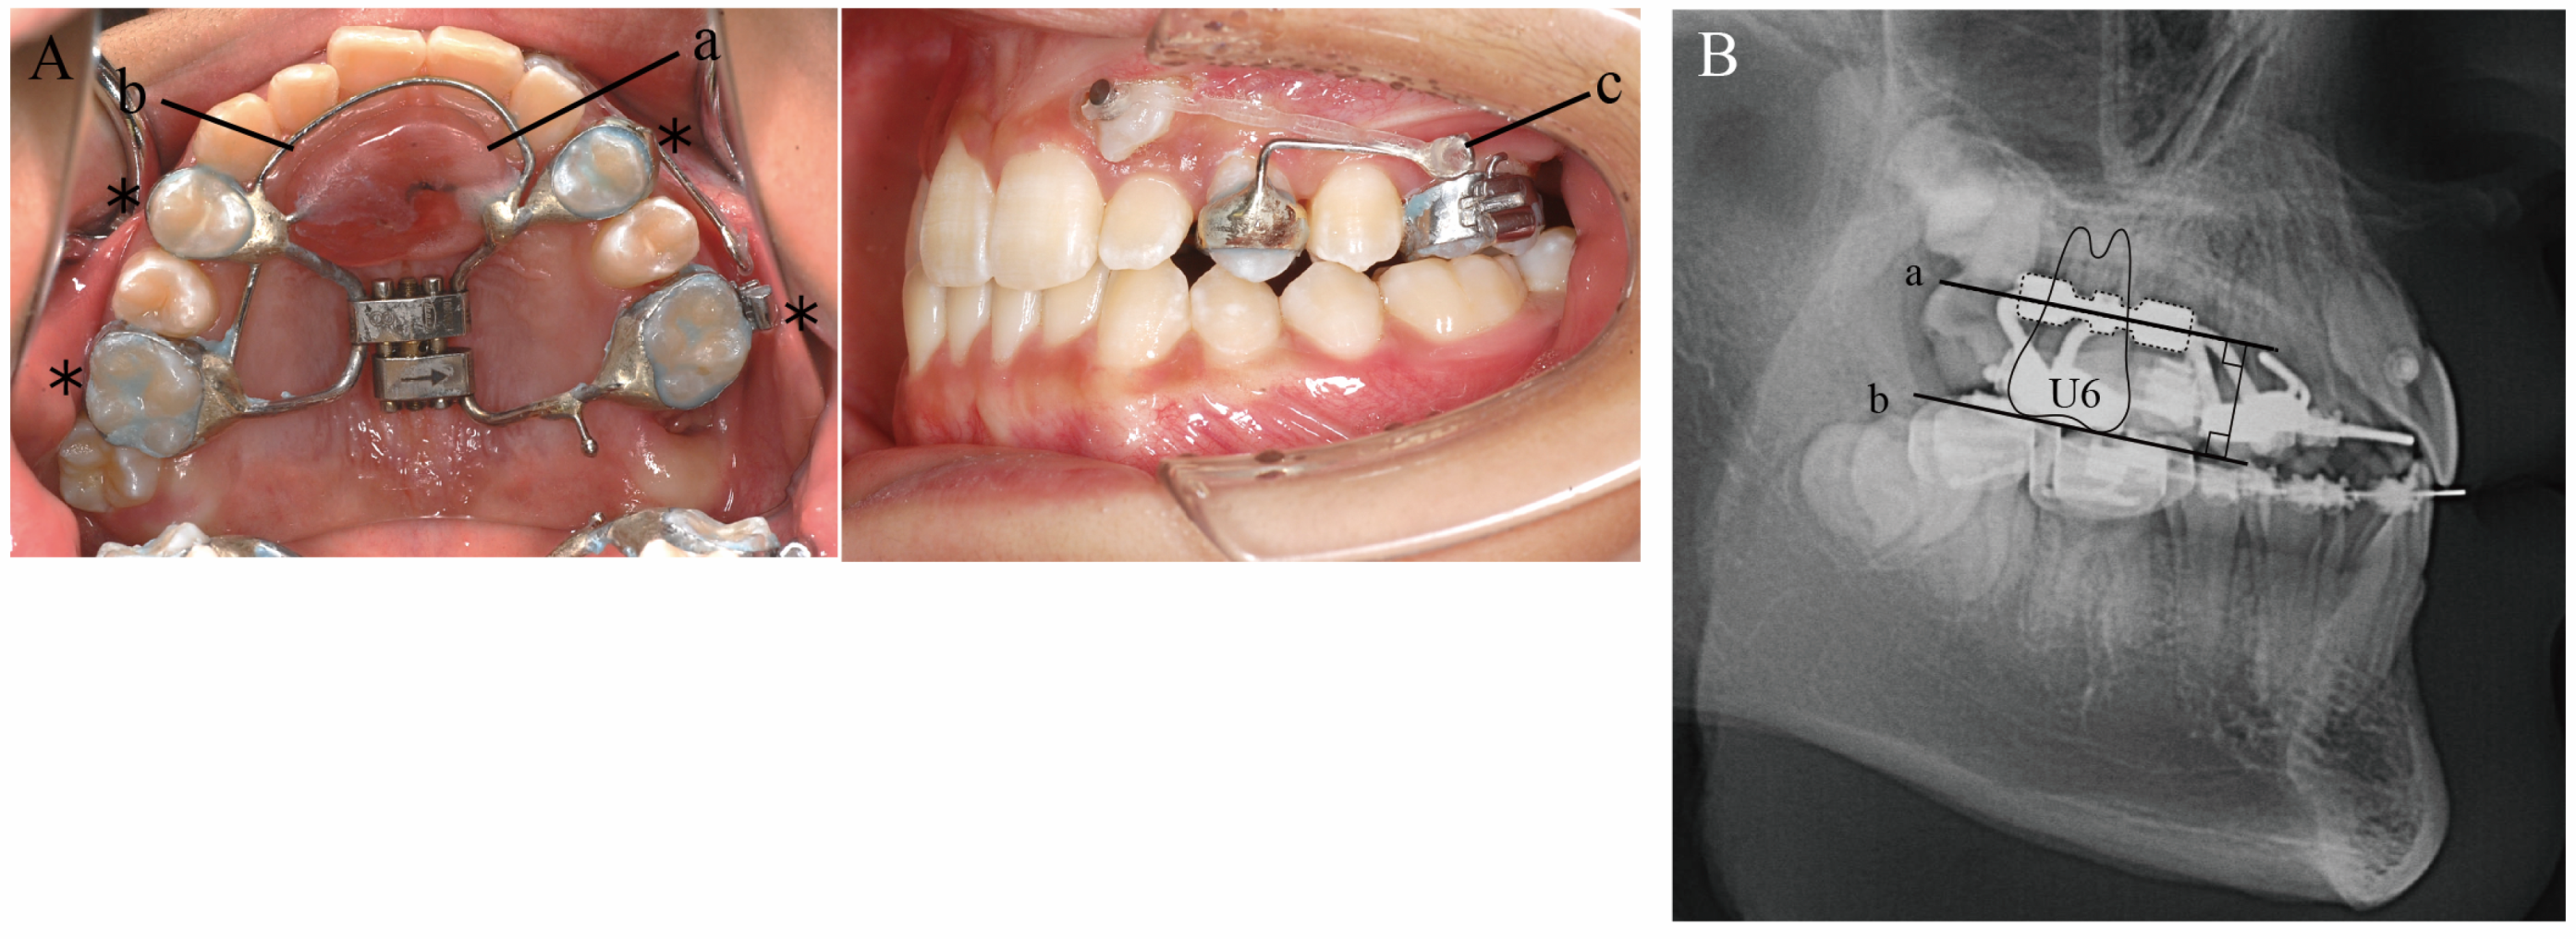

Figure 2. Initial dental casts (age, 14 years 4 months).

The facial features were symmetrical in the frontal view, with the maxillary midline coinciding with the facial midline and the mandibular midline deviated 1.5 mm to the right when smiling. The lateral view showed a straight profile. The occlusal relationship of the first molars was Angle Class I on the right side and Angle Class II on the left side, with overjet of +2.0 mm and overbite of +3.0 mm. The maxillary left canine was displaced to the labial side of the maxillary left lateral incisor, with its apex slightly and ectopically erupted. It was unclear whether the maxillary left deciduous tooth was lost prematurely during the deciduous-to-permanent dentition phase, as neither the patient nor his guardians could remember. Due to the mesial positioning of the maxillary left first molar, there was a lack of eruption space for the maxillary left canine, with an arch length discrepancy of −7.5 mm. The mandibular anterior teeth were slightly crowded, with an arch length discrepancy of −3.0 mm. The maxillary right lateral incisor and mandibular right lateral incisor were in crossbite (Figure 1 and Figure 2).